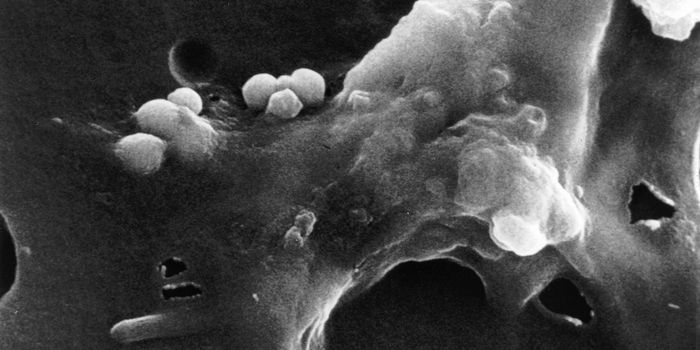

DEC 10, 2015ImmunologySuperior technology brings us novel images of cancer cells and lymphocytes this week, and now scientists can learn more ...